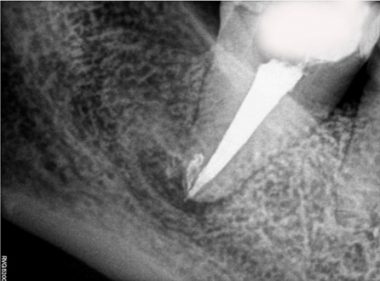

Patient Name: Asha Mane

Tooth Number: 47,48

Diagnosis: Radicular Cyst with 47,48

Treatment : endodontic treatment with 47, Extraction with 48.

File system used : TRUESHAPE 3D, Vortex Blue

Pre-operative

Obturation

After extraction with 48

Follow up after 3 months

Master cone after 1 month

Follow up after 6 months